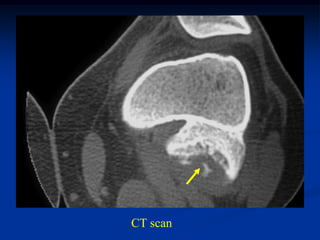

Case #574

2 year male

Ollier’s lower

extremity